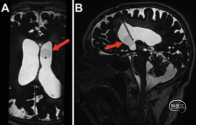

● 一是高分辨率3D SPACE MRI的应用:常规T1或T2加权MR图像上,囊肿内容物信号强度与CSF相似,囊壁通常不清晰,导致IVSN难以诊断。研究人员纳入了高分辨率、重T2加权的3D SPACE(sampling perfection with application-optimized contrast using different flip angle evolutions)序列。结果显示:3D SPACE MRI在所有病例中(100%)都能清晰地显示虫囊包膜,其内容物在3D SPACE图像上呈现出比CSF显著较低的信号强度。

研究确立的综合流程结合了先进影像技术、灵活内镜技术和标准化药物治疗。手术主要目的是恢复CSF循环通路和切除囊肿,所有手术均采用额角入路进入侧脑室。内镜手术不仅包括囊肿切除,还常规实施了内镜下第三脑室底造瘘术(ETV)和透明隔造瘘术(septostomy)。ETV和透明隔造瘘术有助于重建CSF通路,避免脑室腹腔分流管的高失败率。